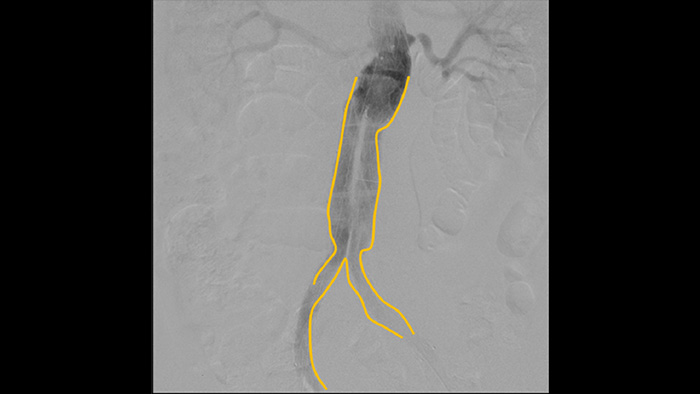

Utilice la herramienta de contorno para marcar con facilidad una bifurcación o las ramas laterales solo dibujando en el monitor de la estación de visualización móvil con el dedo o con un ratón conectado externamente.

La angiografía por sustracción digital (ASD) se utiliza en procedimientos vasculares intervencionistas para ver con claridad los vasos sanguíneos mediante la eliminación de estructuras que pueden oscurecer la visibilidad de los vasos. La hoja de ruta de fluoroscopia superpone la imagen de contraste sustraída con anterioridad adquirida en la fluoroscopia en vivo, lo que le permite rastrear el dispositivo sin reinyectar el contraste.